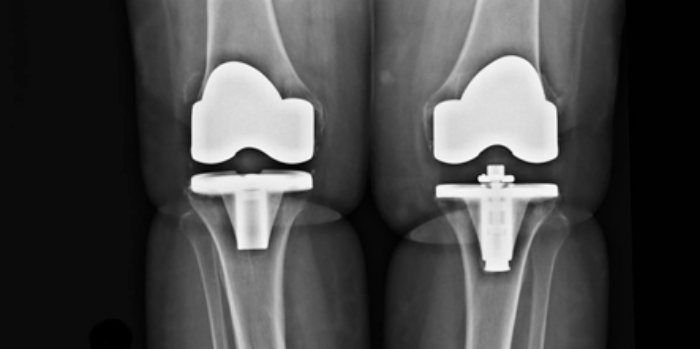

Prótesis de Rodilla

La artrosis de rodilla supone un deterioro progresivo de la función articular. Provoca dolor y una limitación progresiva de la calidad de vida de los pacientes. La cirugía de Prótesis de Rodilla ha supuesto un tremendo avance en cuanto a la recuperación de la calidad de vida de nuestros pacientes y en ayudar a mejorar la función de la articulación.

La cirugía de Prótesis de Rodilla es una de las prácticas más habituales para el Cirujano Ortopédico.  Es importante trabajar con equipos de cirujanos que se dedican habitualmente a implantar y/o recambiar prótesis. Estos equipos están capacitados para resolver todos los problemas que puedan aparecer durante y tras la intervención quirúrgica.

Prótesis de Rodilla. Traumatólogo en Granada. Dr. Eugenio Díaz